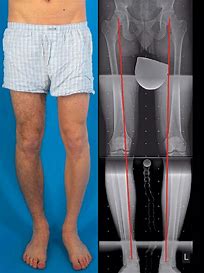

Biomechanics of Knee Osteoarthritis

Knee osteoarthritis (OA) is not only cartilage degeneration; it is strongly influenced by faulty biomechanics, abnormal loading, muscle imbalance, and poor lower-limb alignment.During walking, standing, and stair climbing, the knee bears high loads. When alignment is disturbed, excessive stress falls on one compartment—most commonly the medial compartment—leading to cartilage wear,...

Biomechanics of knee pain

Knee pain and injury often originate proximal to the knee, particularly from the hip and trunk.Impaired trunk control and proprioception, especially in females, are established predictors of knee injury. With growing evidence of hip–knee interdependence, abnormal hip mechanics play a key role in the development and progression of knee osteoarthritis...